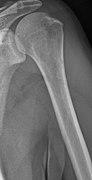

Medical imaging

The diagnostic examination of a person with suspected multiple myeloma typically includes a skeletal survey. This is a series of X-rays of the skull, axial skeleton, and proximal long bones. Myeloma activity sometimes appears as "lytic lesions" (with local disappearance of normal bone due to resorption). And on the skull X-ray as "punched-out lesions" (pepper-pot skull). Lesions may also be sclerotic, which is seen as radiodense.[52] Overall, the radiodensity of myeloma is between −30 and 120 Hounsfield units (HU).[53] Magnetic resonance imaging is more sensitive than simple X-rays in the detection of lytic lesions, and may supersede a skeletal survey, especially when vertebral disease is suspected. Occasionally, a CT scan is performed to measure the size of soft-tissue plasmacytomas. Bone scans are typically not of any additional value in the workup of people with myeloma (no new bone formation; lytic lesions not well visualized on bone scan).